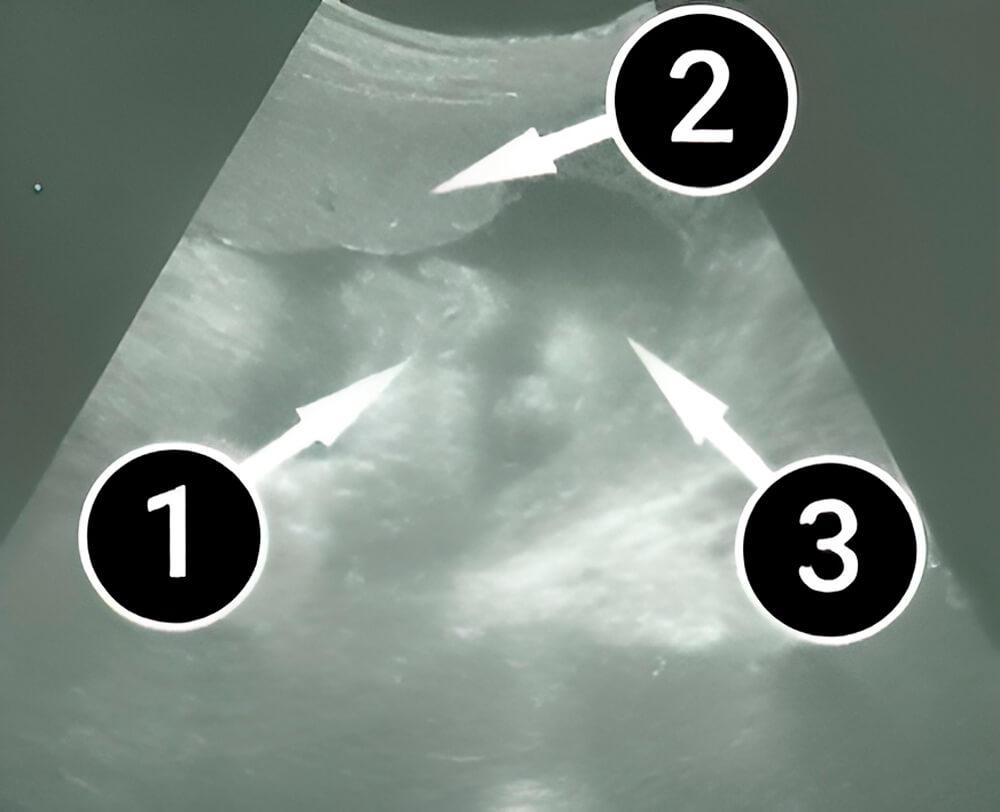

Lo que podemos ver en un ultrasonido

El bebé tiene el lado izquierdo hacia la pantalla. La cabeza es visible a la derecha. También podemos ver la frente, la nariz y el ojo izquierdo. A la izquierda podemos ver sus brazos doblados. La placenta, que ha proporcionado al bebé todo lo necesario para su desarrollo, se encuentra en la parte superior de la imagen.